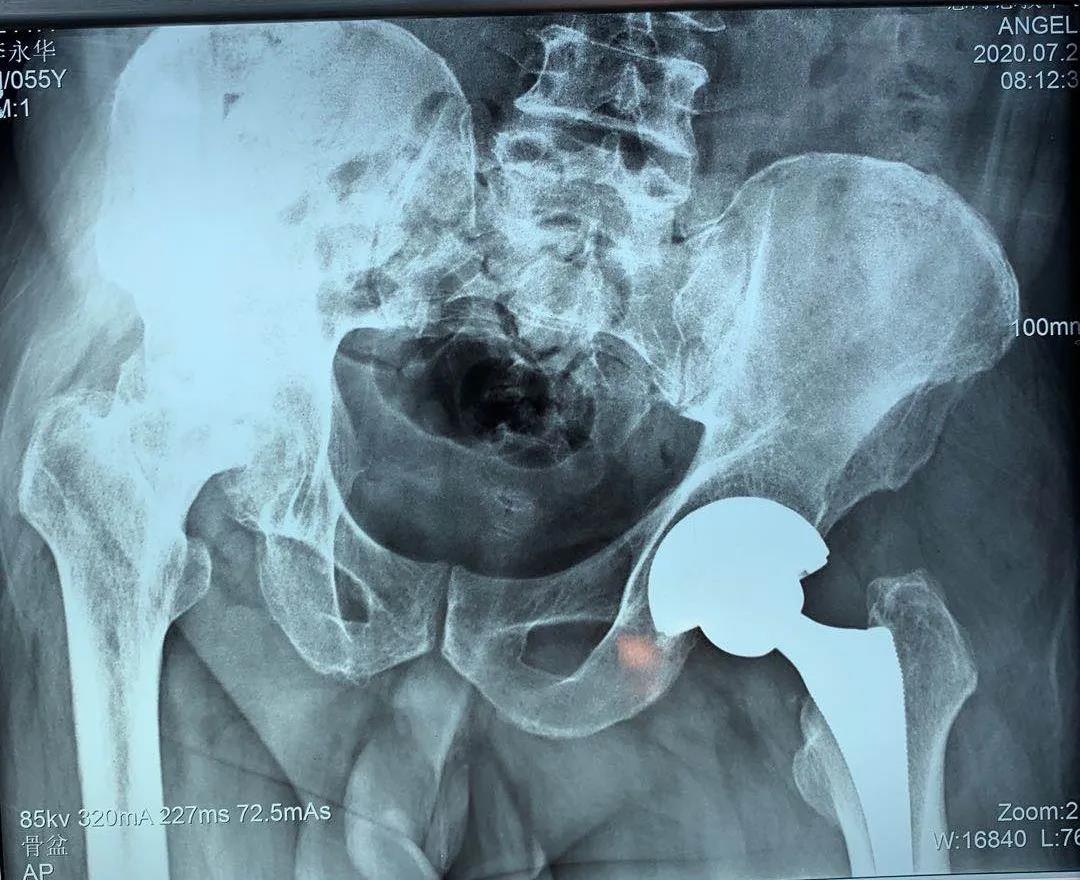

患者一年前雙側(cè)髖疼痛,到骨科就診,確診為股骨頭壞死,由于左髖關(guān)節(jié)痛疼較重給予行左髖關(guān)節(jié)置換,術(shù)后恢復(fù)良好。今年右髖關(guān)節(jié)痛疼加重再次住院,入院后完善相關(guān)檢查,根據(jù)患者病情,征得患者及家屬同意,順利施行了右髖關(guān)節(jié)置換術(shù),術(shù)前片子提示患者骨盆傾斜較重,術(shù)前評估設(shè)計術(shù)中假體植入角度,術(shù)后完美恢復(fù)雙下肢長度與雙側(cè)髖關(guān)節(jié)旋轉(zhuǎn)中心,患者非常滿意,目前患者情況良好,已出院。

術(shù)前拍片

術(shù)前評估骨盆傾斜角度